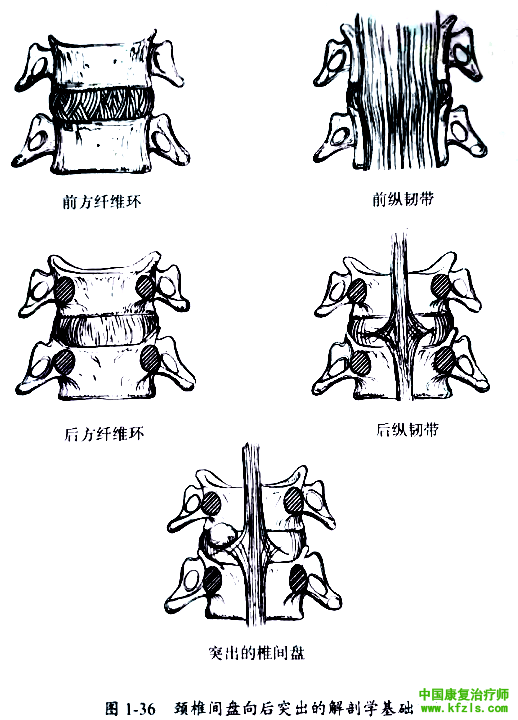

椎间盘只有向后方突出才压迫神经根,解剖学上椎间盘纤维环前方强度大于后方,而且前纵韧带也比后纵韧带宽大和强韧。因此,椎间盘受外力作用后,势必向较为薄弱的后方突出。由于后纵韧带本身为菱形并位于椎间盘后方中央,因此椎间盘常向一侧突出(图1-36),而中央型突出比较少见。